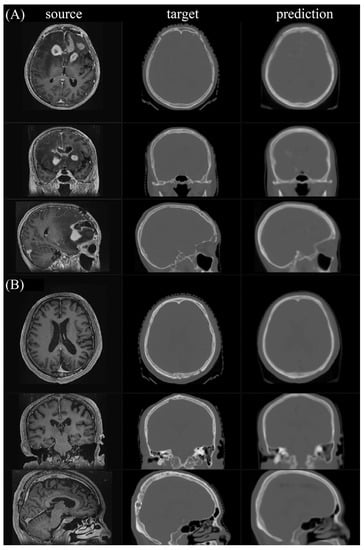

Figure 5 shows the first two testing pairs and their synthetic CT. Each merged prediction is composed of outputs from 15 models. The models of participation are p1_k4_f80, p2_k4_f80, p3_k4_f80, p4_k4_f80, p5_k4_f80, p1_k6_f50, p2_k6_f50, p3_k6_f50, p4_k6_f50, p5_k6_f50, p1_k8_f30, p2_k8_f30, p3_k8_f30, p4_k8_f30, and p5_k8_f30. Because the algorithm is based on a 3D framework, we plot axial, coronal, and sagittal views for each sample. The similarity indices for all tested CT scans and their corresponding synthetic CT scans are shown in Figure 6. The additional two similarity indices, MSE and PSNR, of CT vs. synthetic CT before and after merging were calculated to evaluate the model performance (Supplementary Materials Table S3).

Figure 5. The final merged prediction. (A,B) show the two testing pairs, which are No. 001 and No. 003, and their corresponding merged predictions, respectively.